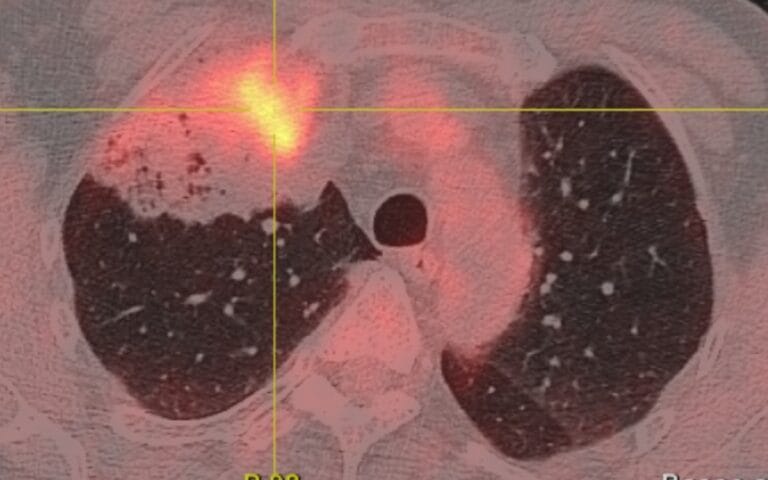

Le dépistage s’appuie sur un scanner thoracique à faible dose d’irradiation. Cet examen permet d’identifier des nodules pulmonaires de petite taille, souvent opérables. Plus un cancer du poumon est diagnostiqué tôt, plus les chances de survie augmentent significativement.

- Intelligence artificielle appliquée à l’imagerie radiologique

L’objectif est de mieux sélectionner les patients les plus à risque avant de les orienter vers un scanner, afin d’optimiser les ressources et d’améliorer la précision du diagnostic précoce.